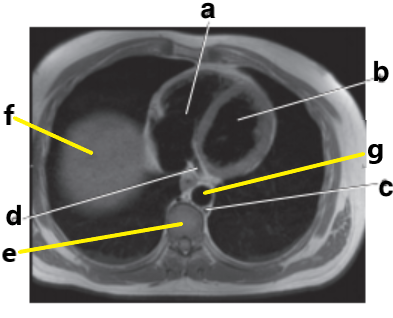

What is letter f ?

Diaphragm

Clavicle

Ribs

What is letter e ?

Vertebral body

What is letter c ?

Hemiazygos vein

Which letter is the descending thoracic aorta ?

e

What is letter g ?

Descending thoracic aorta

Descending aorta

Identify the structure labeled with "e":

Liver

Thoracic vertebra

Sternum